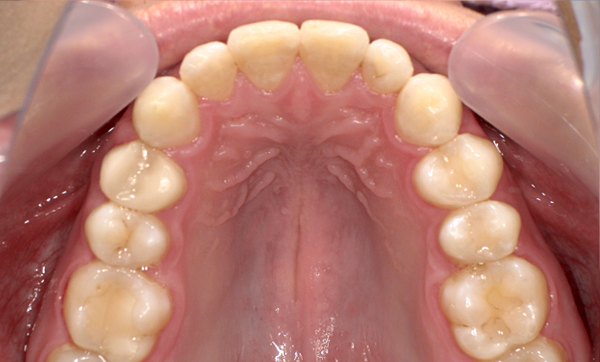

症例_009 「上下の前歯」症例

治療期間:7ヶ月金額:54万円+税20代女性捻転歯一部の反対咬合前歯のガタガタ